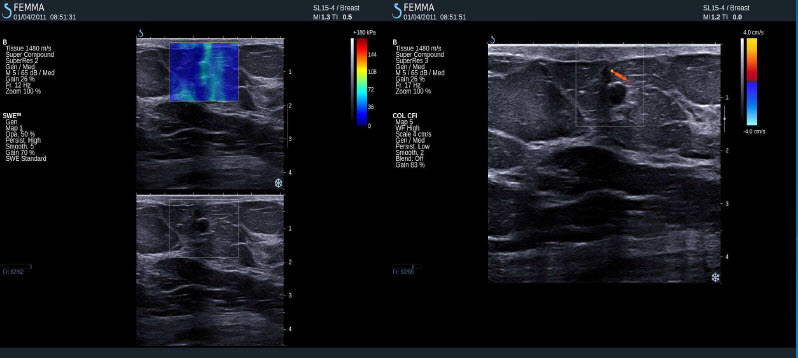

Pozitivní výsledky elastografie / histologicky potvrzená benignita

Intraduktální papilom